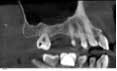

Case 1: Osteotome sinus lift with simultaneous implant placement

A 53-year-old female with a medical history of hypothyroidism, seasonal allergies, and asthma taking Synthroid and Singula presented to my office with pain in No. 3, failed root canal therapy, and a fracture. The tooth was deemed hopeless and extraction and implant placement was treatment planned. Under local anesthesia, tooth No. 3 was sectioned into three pieces and extracted. The sockets were debrided, filled with gel foam, and closed with chromic gut sutures. Healing was uneventful. The patient did not return for two years for follow-up. A CT scan was taken, which confirmed that approximately5 mm of bone remained below the floor of the sinus. After reviewing the options with the patient, a treatment plan of an internal sinus lift (osteotome), bone graft, platelet-rich fibrin (PRF) and simultaneous implant placement was agreed upon. Under local anesthesia, a full thickness flap with two vertical releasing incisions was performed at tooth No. 3 site. A trephine bur was used to a depth of 4 mm. An osteotome was then employed to infracture the bone core, which remained attached to the Schneiderman membrane. A bone graft consisting of DFDBA, anorganic bovine bone, and PRF was used in the osteotomy to increase the vertical bone height using sequential osteotomes. After sufficient elevation, a 7x9 tapered implant was placed on low speed to 50% of the implant depth. The remaining placement of implant was done with a hand torque on 50 ncm to allow for further expansion of the alveolar housing. A healing abutment was placed using the principles of platform switching. Healing was uneventful, and integration was successful.